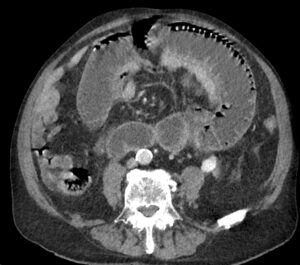

TC axial con contraste IV en fase portal.